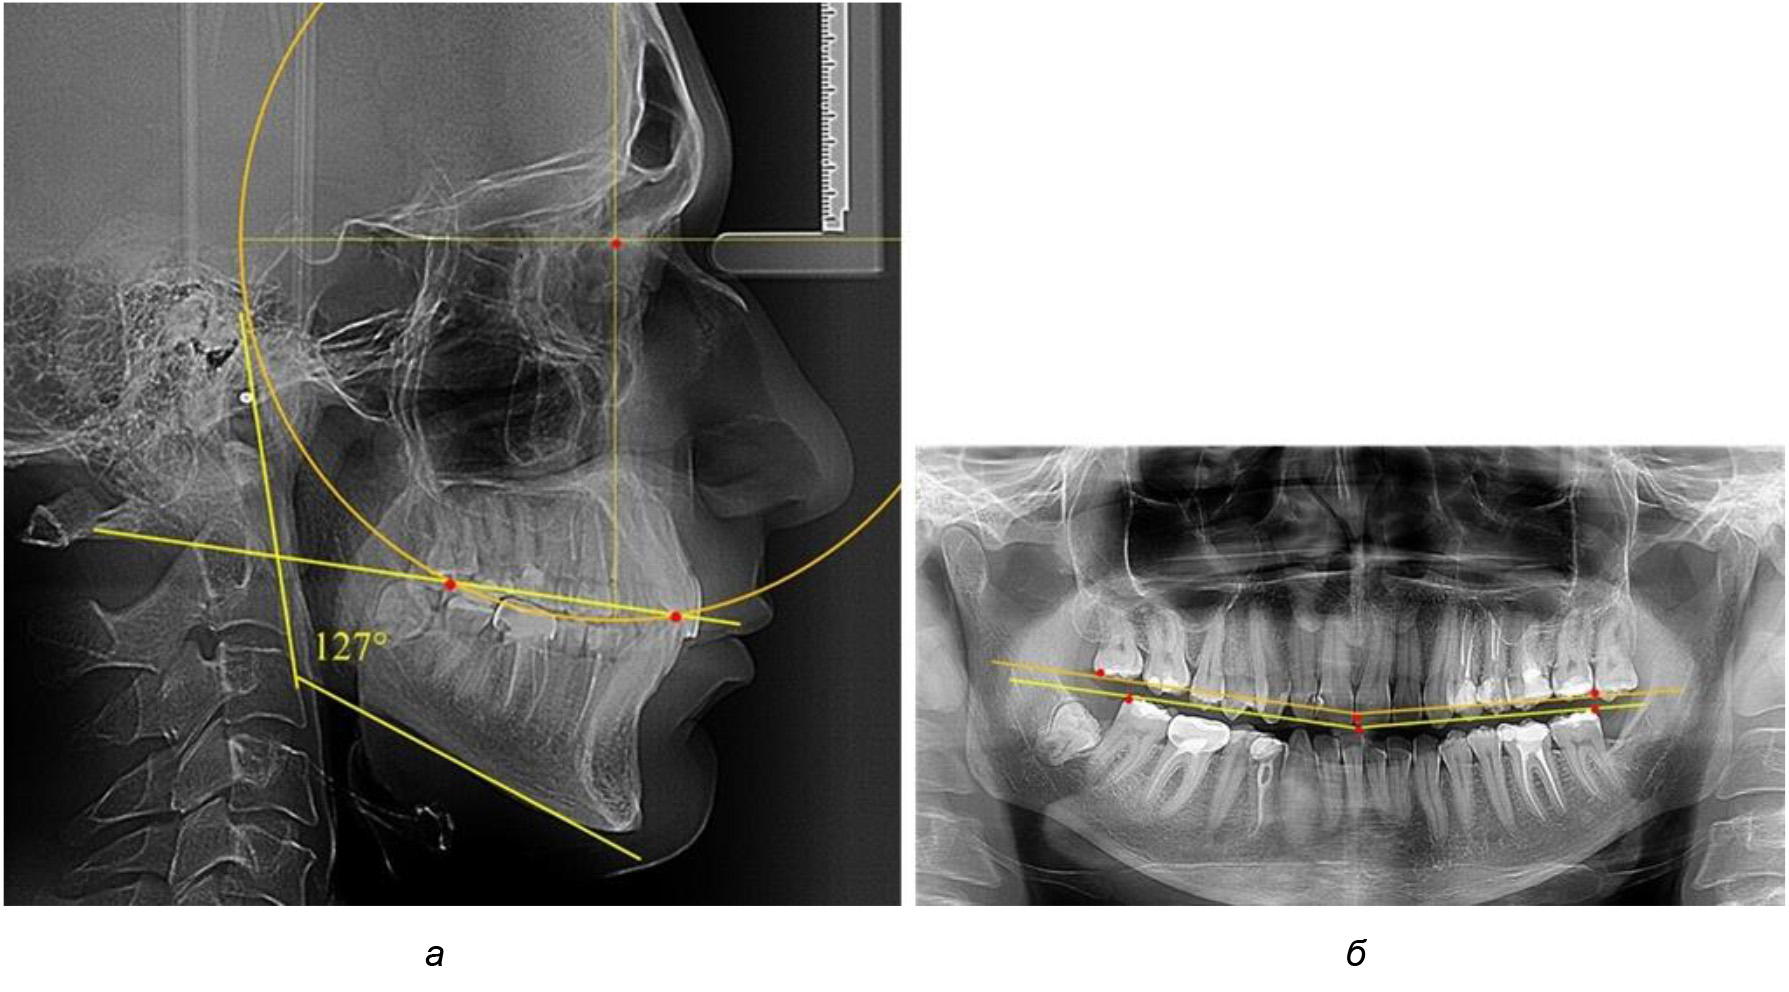

При анализе латеральных ТРГ устанавливали реперный окклюзионные точки в переднем и боковом отделе. Передняя точка устанавливалась на режущем крае нижнего медиального резца, которую в клинике ортодонтии обозначают как vPOcP. Дистальная точка второго нижнего моляра обозначалась как hPOcP. Измеряли расстояние между окклюзионными точками, что определяло сагиттальный размер окклюзионной линии. Использование программ PowerPoint позволило проводить окружность, проходящую по линии смыкания зубов через окклюзионные точки. Измеряли радиус окружности. Учитывая вариабельность размеров окклюзионной линии и радиуса окружности, определяли относительный показатель через отношение радиуса круга к длине сагиттального размера окклюзионной линии. Глубину окклюзионной кривой измеряли от точки наибольшей выпуклости до окклюзионной линии (рис. 1). На ортопантомограмме (ОПТГ) также соединяли окклюзионные точки правой и левой стороны и измеряли глубину окклюзионной кривой от точки наибольшей выпуклости до окклюзионной прямой линии. Результаты глубины кривой Spee сравнивали по данным ТРГ и ОПТГ.

Рис. 1. Метод определения кривой Spee на ТРГ (а) и на ОПТГ (б)